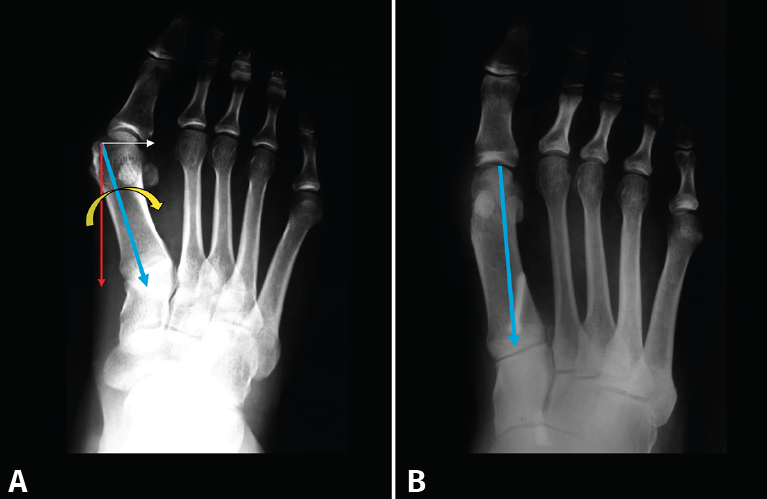

Figura 7. A: Cuando M1 se desvía en varo, la fuerza de reacción del suelo provoca en la primera tarsometatarsiana una dorsiflexión y una rotación externa; B: la osteotomía lateralizadora contribuye a estabilizar la articulación.

Como vemos, la 1.ª ATMT está muy bien preparada para soportar las fuerzas de compresión y tensión. En cambio, su morfología no está preparada para soportar fuerzas de rotación en el plano frontal. Cuando M1 está desviado en aducción-varo (Figura 7A), la fuerza de reacción del suelo que recibe provocará a nivel de la 1.ª ATMT una dorsiflexión en el plano sagital y una rotación externa en el plano frontal. Ambos movimientos se ven aumentados a medida que aumenta la aducción del metatarsiano. En estudios sobre cadáver(10), se ha comprobado que, en el hallux valgus, al realizar una osteotomía lateralizadora de M1, la primera TMT se estabiliza, oponiéndose mejor a las fuerzas dorsiflexoras (Figura 7B).